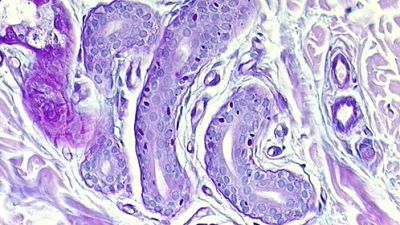

La enfermedad de Lafora es un tipo raro de epilepsia mioclónica progresiva que describió en 1911 el neuropatólogo español Gonzalo Rodríguez Lafora.

Se manifiesta con una serie de crisis epilépticas que, con el tiempo, afectan a distintas partes del sistema nervioso. Estas llegan a producir desmayos, alucinaciones, demencia y, finalmente, la muerte de los pacientes principalmente por fallos del sistema respiratorio.